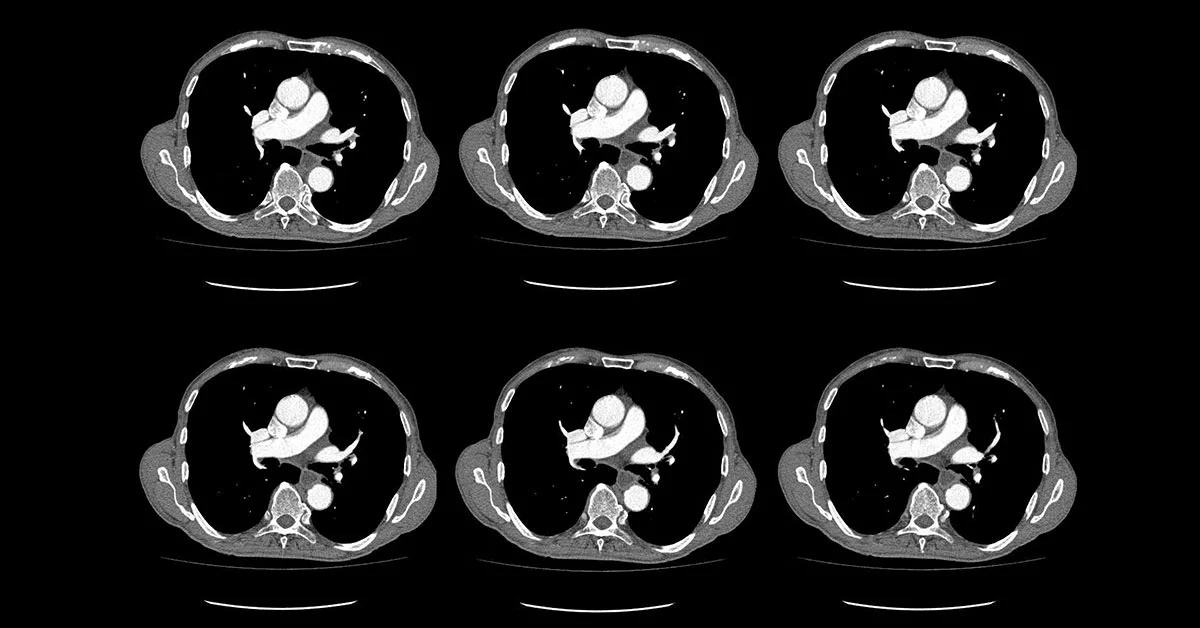

Angiotomografia de Tórax

O termo angiotomografia de tórax acaba sendo usado como sinônimo do exame de Angiotomografia das Artérias Pulmonares, ou Protocolo de Tromboembolismo Pulmonar (TEP), no jargão médico. É um exame de imagem dedicado à procura de sinais de trombos agudos e crônicos na circulação arterial pulmonar de suas consequências, como sobrecarga das câmaras cardíacas direitas e infartos do parênquima pulmonar.